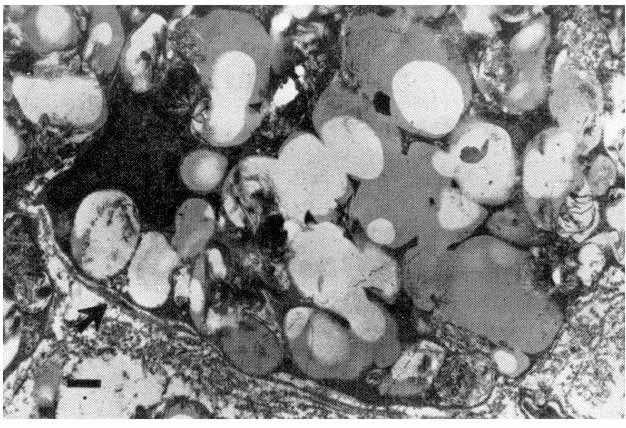

Monocitni klirens sistem” Metabolizam lipoproteina u nivou intime je vrlo složen. Mora postojati balans između lipoproteina koji ulaze u intimu i njihovog odstranjivanja iz nje. To je uloga “monocitnog klirens sistema”. Aktivirani monociti, kao i transformisane glatke mišićne ćelije postaju makrofazi i odstranjuju suvišne lipoproteine. Propterećeni makrofazi postaju “penušave ćelije” i više nisu u stanju da putem svojih lizozomalnih enzima razaraju endocitovane lipoproteine. Tada “penušave ćelije” prestaju da budu funkcionalni deo “monocitnog klirens sistema” i postaju oružje autodestrukcije. Citonekroza makrofaga dovodi do pro- sipanja lizozomalnih enzima. Nastaje lokalna tkivna nekroza, sa egzacerbacijom arterogeneze, pucanjem bazalne membrane i iniciranjem nestabilnosti plaka.

“Penušave ćelije” u mediji ateromatozne arterije sa ekscesnim sadržajem lipoproteina u fegocitoznim vakuolama